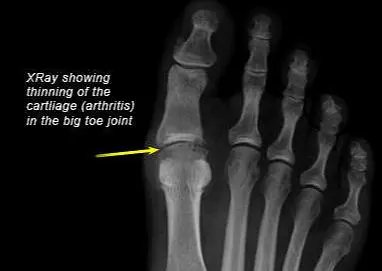

骨关节炎的病理基础是关节软骨的磨损,随着病情的加重,软骨磨损会越来越重,关节的间隙就会越来越狭窄,那么我们的身体为了让关节更加的稳定,就会慢慢的形成骨赘,也就是我们都耳熟能详的骨质增生、骨刺,来帮助增加关节的面积,增加关节的稳定性,但如果这骨赘形成的太多,就有可能影响到周边的软组织以及血供。

●如果不影响行走,肿痛还能够接受,应该去医院在医生的帮助下进行足踝部的x线检查,明确是否存在骨赘,形成是否关节间隙有狭窄。

而比如骨关节炎,类风湿关节炎这些问题,相对来讲发病不会特别的急骤,肿胀相对比较明显,疼痛可能会略轻一点。如果是这些情况,应该在医生的帮助下进行相应的检查,比如x线,比如采血化验风湿、类风湿的相关项目检查来明确诊断。